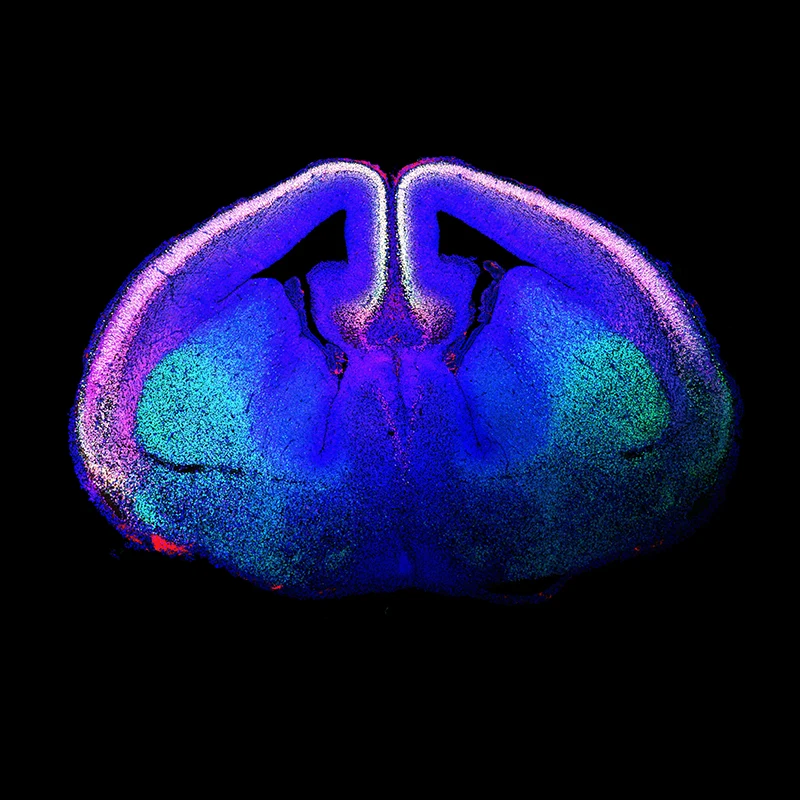

Figure 1. “Rising Life" shows a developing mouse brain, with newborn glutamatergic neurons of the cerebral cortex labeled using immunofluorescence techniques and shown in white. The labeled proteins are CTIP2 (green) and TBR1 (red), with the DNA marker DAPI (blue). White nuclei are glutamatergic neurons that stain for all three. Courtesy of Marta Garcia-Forn, PhD, Postdoctoral Fellow, De Rubeis Lab.